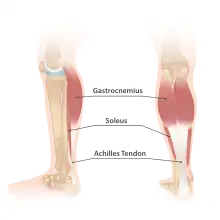

- (anatomy) Achilles tendon (strong tendon formed of the united tendons of the large muscles in the calf of the leg)

- Achilles-ín-szakadás ― Achilles tendon rupture